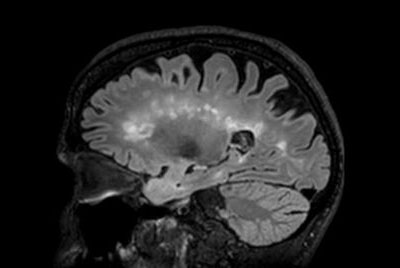

Alzheimer’s Disease Anti-Amyloid Immunotherapies (ARIA) 3.0T